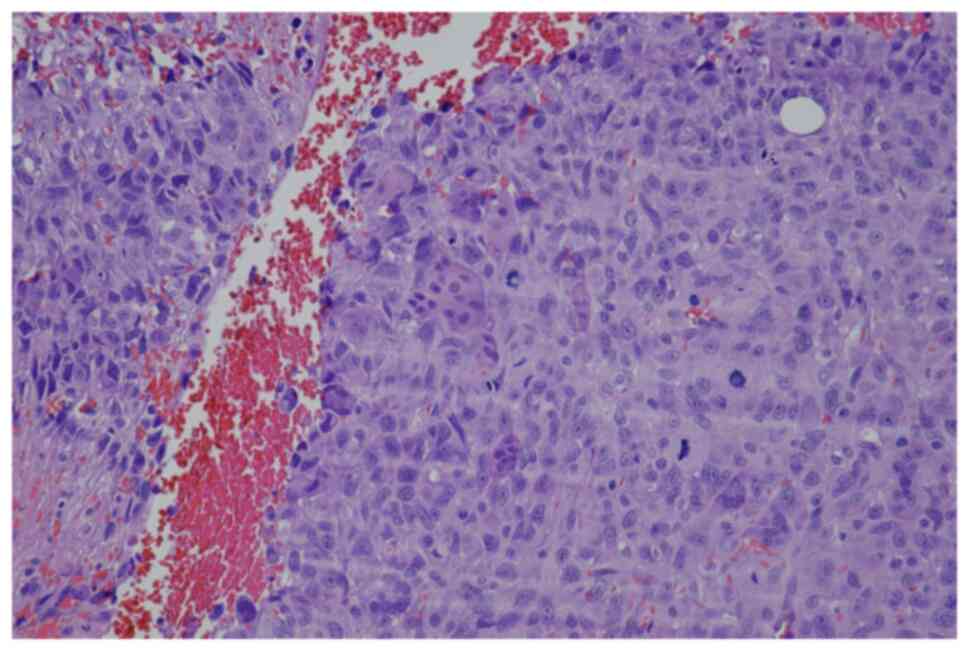

In June 2007, a 50-year-old male presented to the Masaryk Memorial Cancer Institute Sarcoma Center, with a 1-month history of persistent pain in the right ankle. Further investigations showed a cystic lesion of the talus on a CR scan, which was later confirmed by a supplementary CT scan (Fig. 16). The histopathology report diagnosed GCTB with a secondary aneurysmal cyst of the talus (Fig. 17), leading to a recommendation for intralesional resection with bone cement augmentation. After receiving the recommended treatment, the patient returned 5 months later with swelling and increased pain in the ankle. A follow-up CT scan showed destruction of the bone surrounding the bone cement, as well as osteolysis of the calcaneus and the presence of an extraosseous mass proximally (Figs. 16 and 18). Due to the extent of osteolysis, the patient required an astragalectomy. Subsequent histopathology reports showed a diagnosis of giant-cell rich osteosarcoma, contradicting the initial findings (Fig. 19). Further staging scans indicated the presence of lung metastases (Fig. 20). The Musculoskeletal Tumor Committee recommended metastasectomy followed by adjuvant CHT. Despite the successful removal of 12 lung metastases, the patient developed additional lung metastases within two months. Despite palliative care efforts, the patient died 6 months later.

Case 4. Hematoxylin and eosin staining of an open biopsy. Magnification, ×100. Fragmented biopsy of giant-cell tumor of bone without malignant features, joined by lamellae of fibrous tissue, foci of hemorrhage and solitary granules of hemosiderotic pigmentation.

Case 4. Hematoxylin and eosin staining of the resected talus. Magnification, ×100. A highly cellular malignancy was shown characterized by eosinophilic lace-like osteoid interwoven with numerous giant multinucleated cells, consistent with giant cell-rich osteosarcoma.